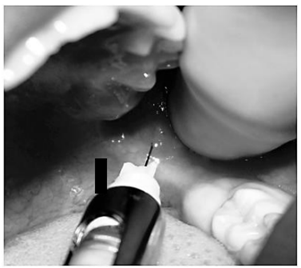

É imprescindível anestesiar todos os dentes

que passarão por qualquer procedimento

endodôntico. Essa exigência fundamenta-se na

possibilidade de o paciente experimentar

sensibilidade durante a realização do

procedimento, o que pode comprometer sua

execução adequada.

Analisando a imagem acima, podemos afirmar que a técnica usada para anestesia dos dentes inferiores foi: